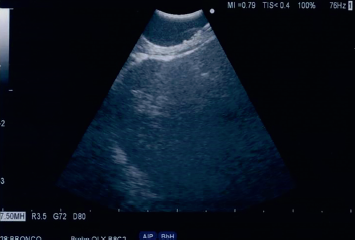

Paziente di 79 anni veniva ricoverata per l’insorgenza di disfagia. Durante la degenza la paziente praticava TC total body con mdc con riscontro di grossolano espanso del mediastino posteriore adeso all’esofago (Figura 4) e PET TC con evidenza di intensa attività metabolica in corrispondenza della suddetta lesione (SUV max 15,56). L’esame spirometrico e l’emogasanalisi risultavano nella norma. L’ecocardiogramma confermava la presenza di una massa comprimente l’atrio sinistro. La paziente veniva sottoposta ad esame broncoscopico in anestesia generale: l’esplorazione dei territori bronchiali non mostrava alterazioni degne di nota. Si introduceva, quindi, l’ecobroncoscopio in esofago (EUS-B) con localizzazione di massa paraesofagea destra che si procedeva a campionare (FNA) (Figura 5). La valutazione estemporanea del campione (ROSE) documentava l’adeguatezza del prelievo. Il materiale veniva quindi posto in provetta da Thin Prep per esame citologico. L’UOC di Anatomia Patologica avrebbe quindi confermato la diagnosi di neoplasia mesenchimale maligna (Figura 6).

Figura 5.EUS-B. Immagine ecografica della formazione del mediastino posteriore.